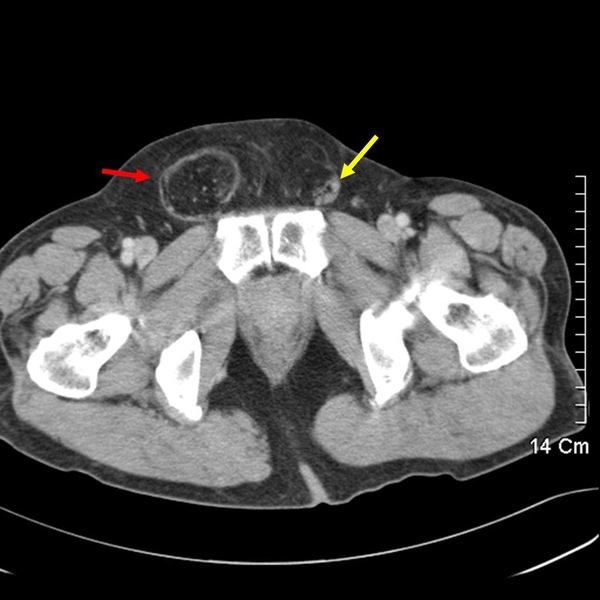

上圖紅色箭頭處圓圓大大黑黑的便是腹股溝疝氣,因為他疝氣囊裡的是大網膜,所以是黑色的一大坨。(小小複習:請問黃色箭頭指的是?您可以在男生女生大不同 裡找到答案。)

讓咱們換個切面來看,可以見到一長串墜入陰囊內的便是大網膜。從這張圖裡可以見到相當健壯的肌肉,可以推測是為壯年男性,或許是健身,或許是勞力工作,因使氣力會讓腹壓上升,加劇疝氣的程度。